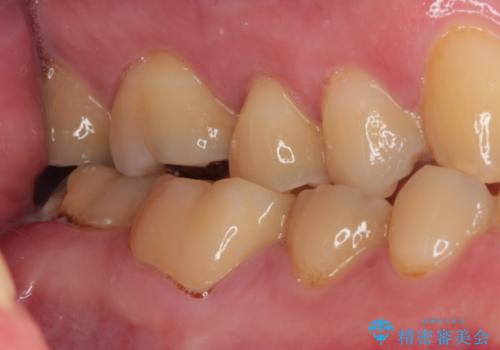

- 東南アジアへの長期赴任を前に、以前から気になっていたむし歯を治療したいとのことで来院された患者様です。

レントゲン写真から、神経の近くにまでむし歯が及んでいる様子が分かり、範囲も広範囲であったので、まずは仮歯に置き換え、その後オールセラミッククラウンにて補綴治療を行うこととしました。

処置を開始するに当たり検査診断を行ったところ、歯髄組織にまでむし歯が及んでいる可能性が示唆されたため、万が一の事態に備えてラバーダム装着による無菌的環境にて虫歯除去を行うこととしました。

虫歯は歯髄組織のギリギリにまで及んでいたものの、歯髄組織が露出することはなく、処置から数日経った日に行った検査でも歯髄組織の異常所見は認めれらませんでした。

速やかに補綴治療を行い、無事に海外赴任前に治療を終えることができました。